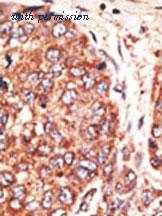

gene information - human SEPT9

- description:septin 9